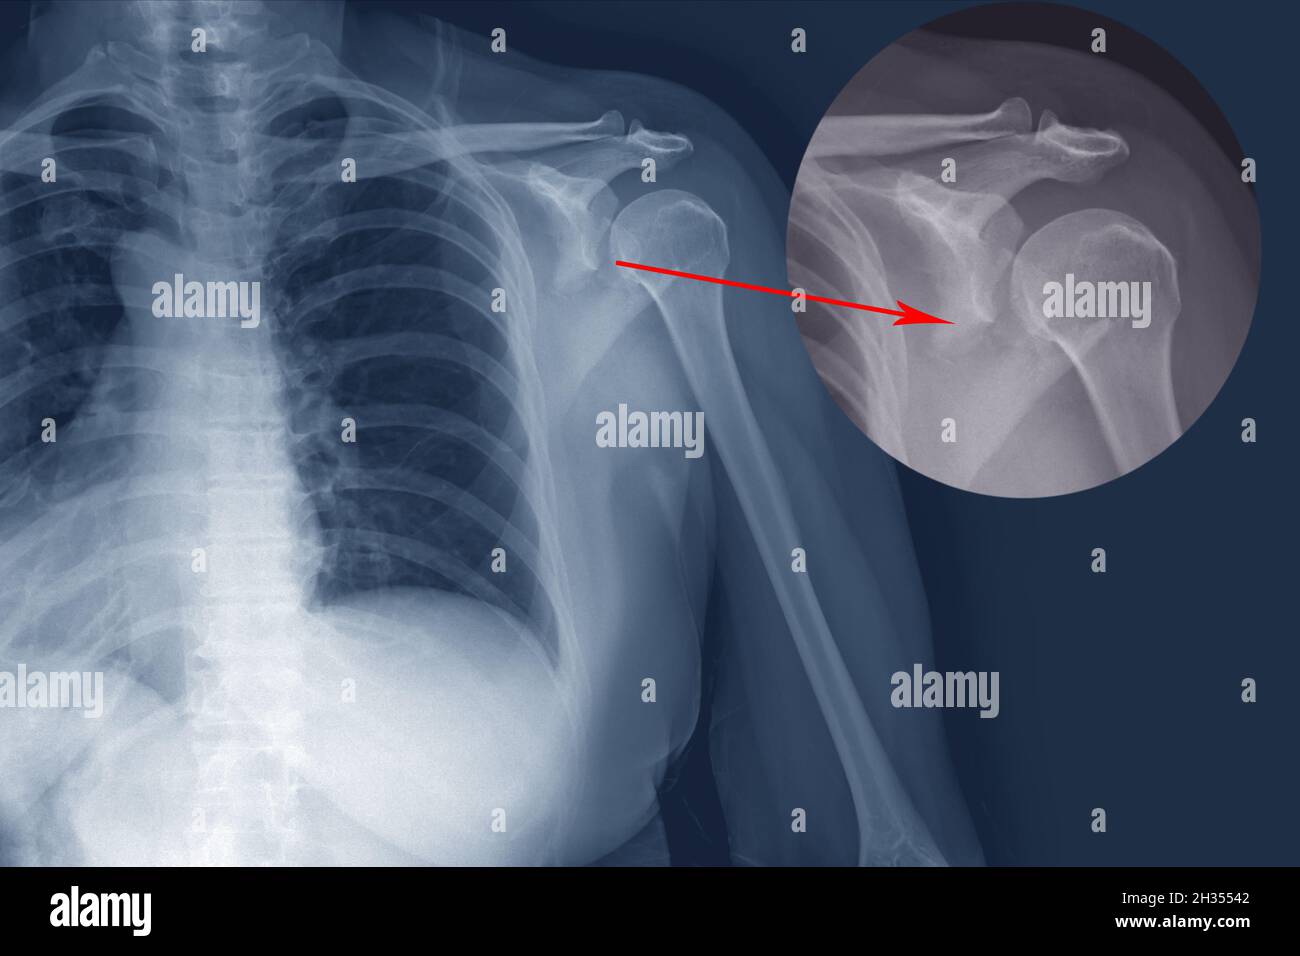

RF2H35542–Frattura della spalla radiogena metà posteriore del glenoide con dislocazione posteriore del frammento osseo. Frattura trasversale irregolare nel corpo della scapola.